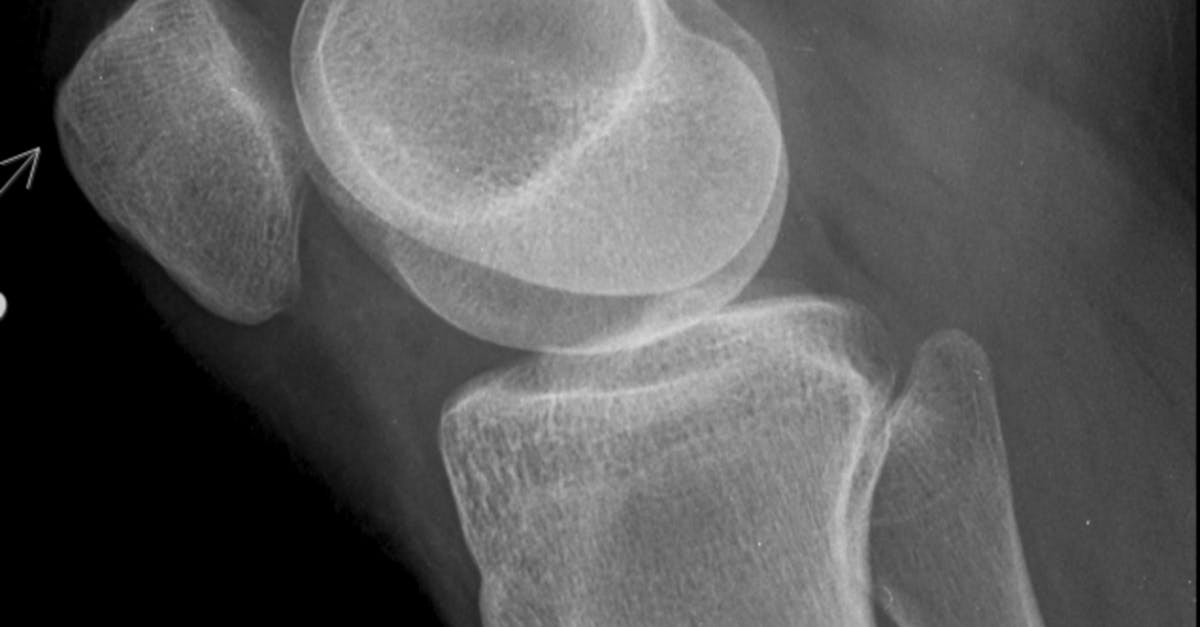

9. Knee Valgus - The Inward Collapse Pattern

Knee valgus, characterized by the inward angulation of the knees toward the midline, represents a significant postural and movement pattern dysfunction that affects both static alignment and dynamic movement quality. This condition, commonly observed during weight-bearing activities such as squatting, landing, and single-leg stance, creates substantial biomechanical stress throughout the lower extremity kinetic chain and is strongly associated with increased injury risk, particularly anterior cruciate ligament (ACL) tears and patellofemoral pain syndrome. Research utilizing three-dimensional motion analysis has identified multiple contributing factors to knee valgus, including hip abductor weakness, gluteus medius dysfunction, ankle mobility restrictions, and altered neuromuscular control patterns. The biomechanical consequences of knee valgus extend beyond the knee joint itself, creating altered loading patterns at the hip, patellofemoral joint, and ankle complex. Clinical studies have demonstrated that excessive knee valgus increases lateral patellofemoral contact pressure by up to 45%, contributing to cartilage degeneration and chronic pain. Furthermore, the condition affects the entire lower extremity alignment, often accompanied by femoral internal rotation, tibial external rotation, and foot pronation, creating a predictable pattern of dysfunction known as lower crossed syndrome. Electromyographic research has revealed that individuals with knee valgus demonstrate reduced gluteus medius and gluteus maximus activation during functional movements, combined with increased tensor fasciae latae and quadriceps dominance. The postural implications of knee valgus extend to standing alignment, where chronic valgus positioning can lead to adaptive shortening of the iliotibial band, lateral retinaculum, and hip adductors, while creating compensatory lengthening and weakness in the hip abductors and external rotators.